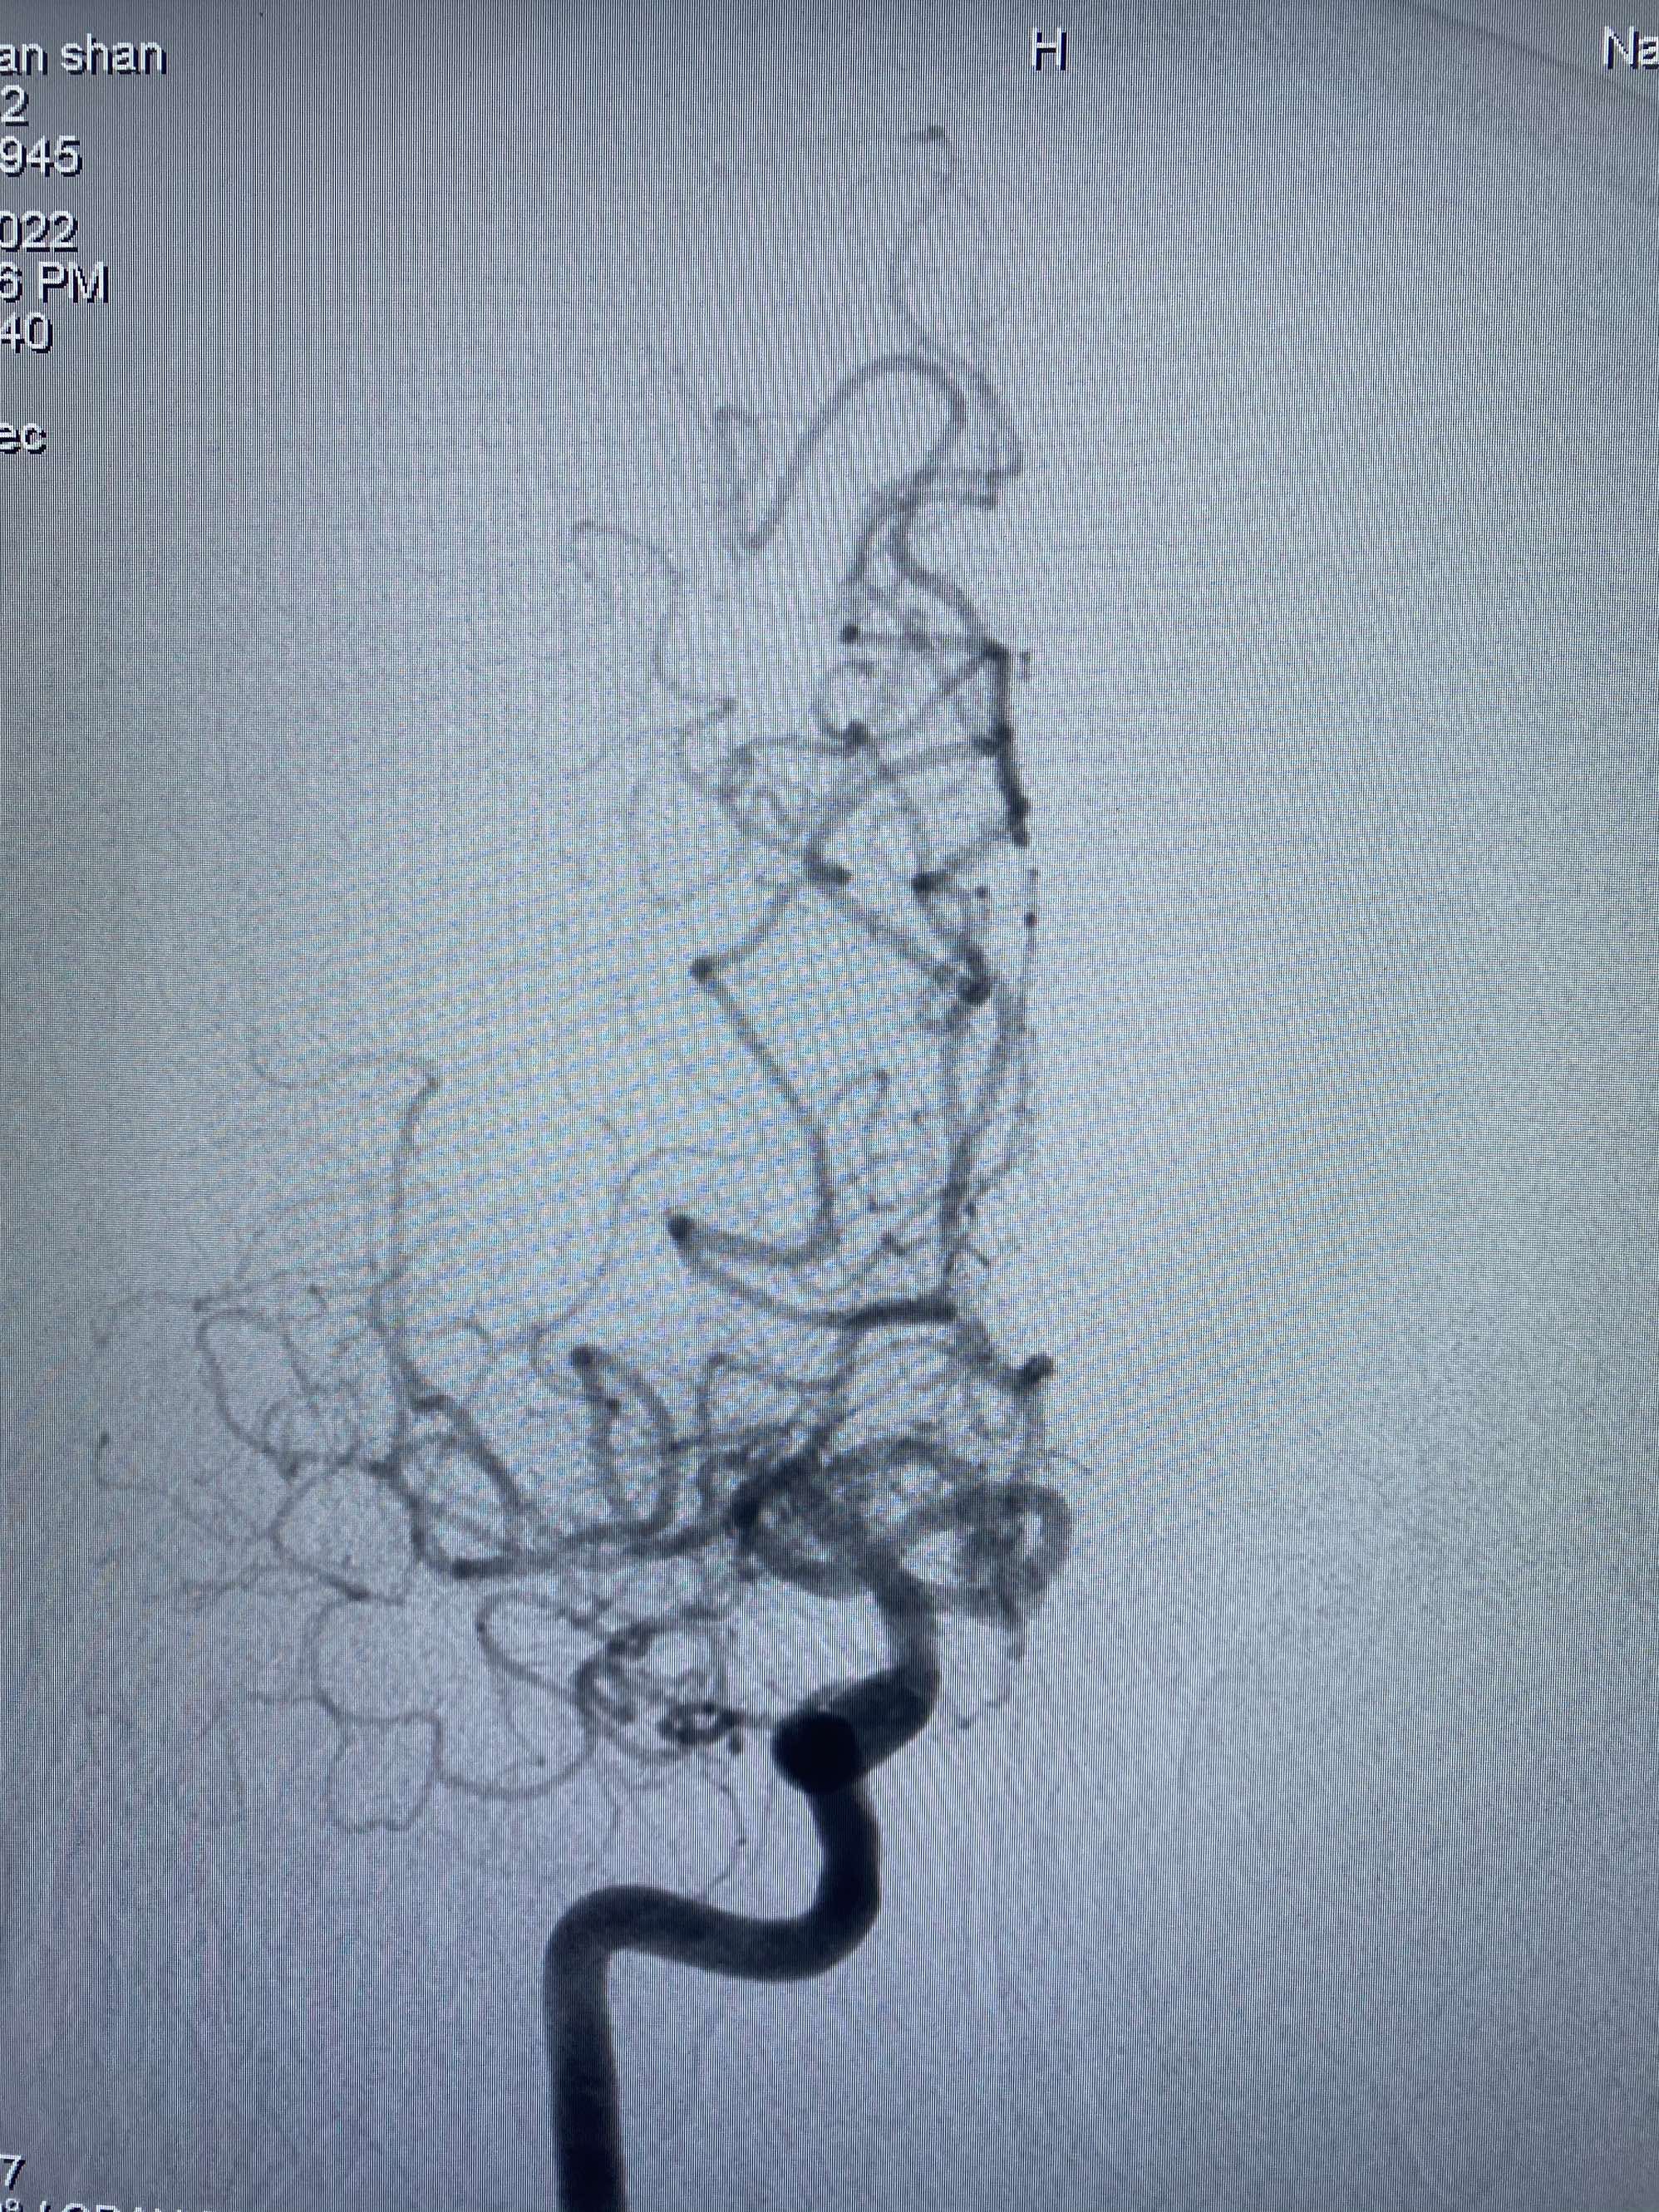

MLS,M79Y,sah,双侧MCA烟雾病,Heubner返动脉瘤,前交通段开窗,细支发出Heubner返动脉,瘤颈细长,瘤颈口比微导管细,弹簧圈2mmx3cm“隔山打牛”填塞治愈,Heubner返动脉保留。

Heubner返动脉是由大脑前动脉A1末端发出的豆纹动脉,由于走形和A1段相反,故称Heubner返动脉,该动脉梗塞可能引起尾状核头梗塞,引起偏瘫和面瘫,便身震颤等症状。